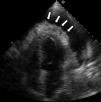

Sarcoma granulocítico (cloroma) cardiaco. Una extraña causa de derrame pericárdico

Cardiac granulocytic sarcoma (chloroma). A rare cause of pericardial effusion